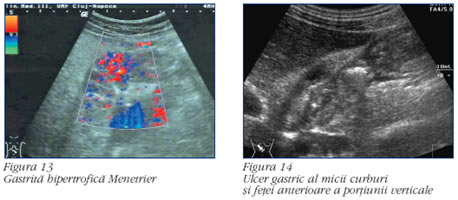

Boala ulceroasa. Diagnosticul ecografic al ulcerului gastric, in context clinic evocator, este sugerat de semne directe sau indirecte

Semnele directe sunt reprezentate de:

a. imaginea ecogena "ancorata" in peretele gastric sau duodenal, masurabila, persistenta, corespunzand nisei (figura 14);

b. reverberatii cu punctul de plecare in nisa.

Peristaltica este normala. Uneori se pot diagnostica microadenopatii inflamatorii dispuse perigastric. Aspectele descrise apar in ulcerul activ, dar nu pot exclude nisa maligna (in cazul localizarii gastrice). Este necesara confirmarea endoscopica si prelevarea materialului tisular in vederea efectuarii examenului histopatologic(1, 11).